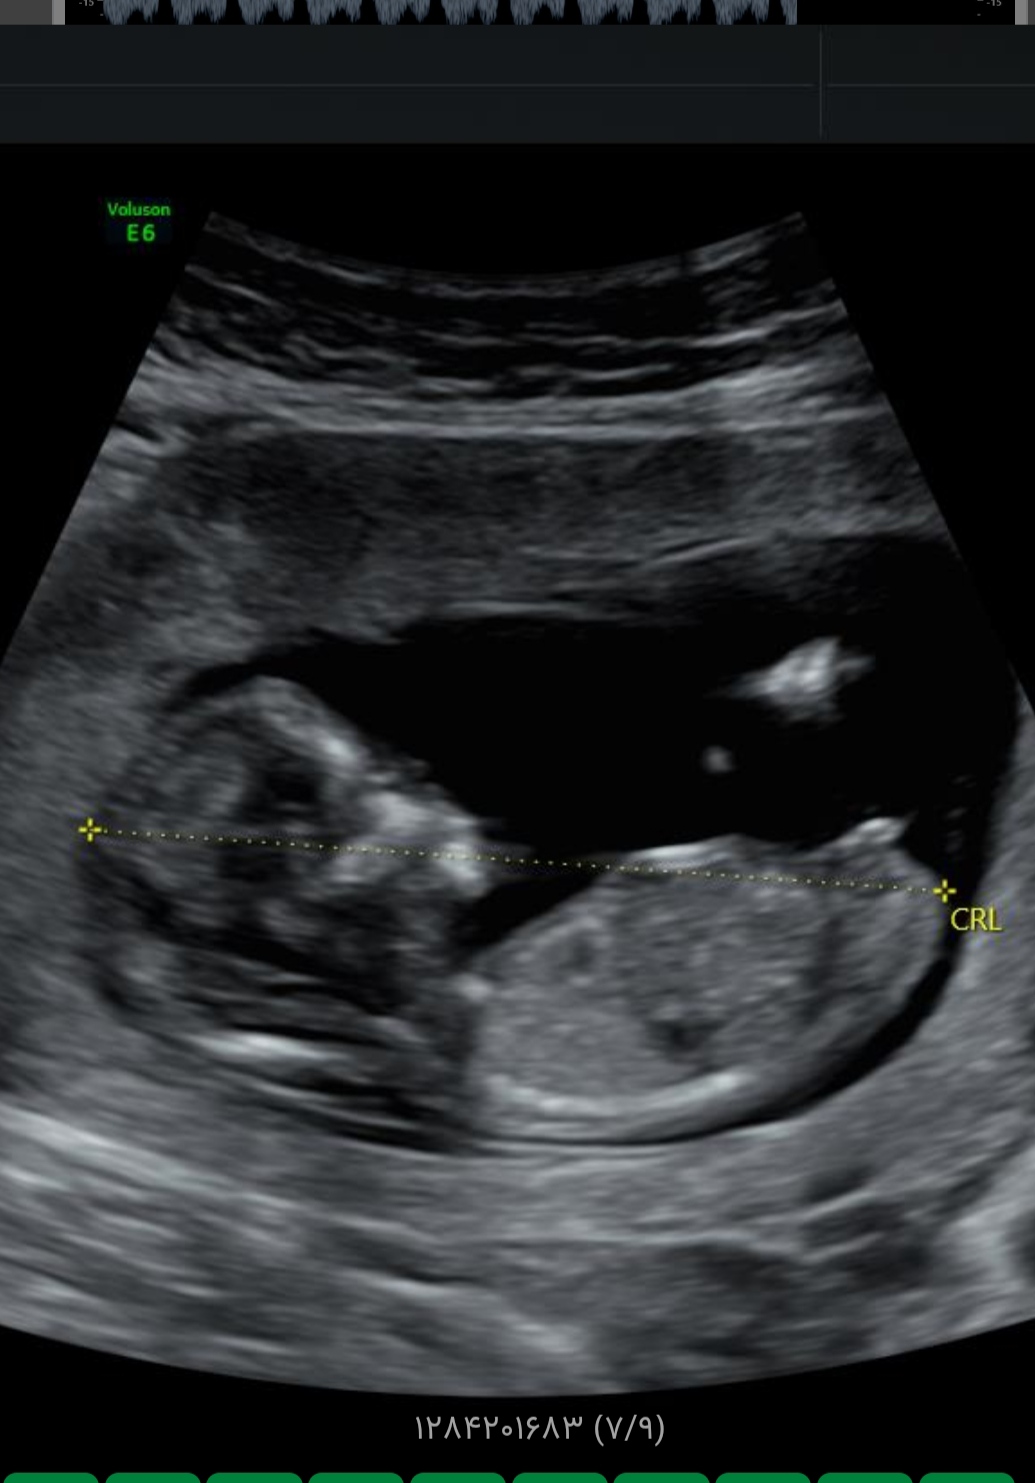

ولی حس میکنم دختره

فقط 9 هفته و 3 روز به تولد باقی مونده !